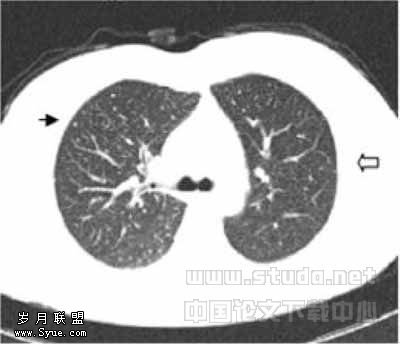

结节的大小、CT扫描参数、图像噪音等影响CT发现肺结节的因素中,以结节大小最重要[11]。Schweden等[12]的研究表明:单排螺旋CT的LD (30mA)与SD (200mA)扫描发现肺结节具有较好的一致性,分歧多数发生在邻近血管的肺结节。Diederich等[13]指出单排螺旋CT的SD与LD扫描发现直径≤5mm、6~10mm、>10mm肺结节的数量无统计学差异;如果LDCT放射剂量太低(25mA,螺距2),图像可能出现伪影,干扰≤5mm肺结节的观察。本文LD与SD扫描发现肺结节均具有较好的一致性,差异主要发生在<5mm的小结节:部分SDCT可见的肯定或模糊的小结节,LDCT显示模糊或未见到(图3,4);部分LDCT显示肯定或模糊的小结节,在SDCT显示模糊或未见到(图5,6);LDCT显示粟粒结节或密度较淡的小结节不如SDCT。另外本文中组的Kappa值略低于B组,但LD1扫描的实际emAs均值却略高于LD2,这与随着emAs降低,图像噪声将增加,影响发现肺小病变的理论不符。我们重新查阅原始资料,发现A组直径<5mm肺结节中粟粒结节和密度较淡的小结节明显多于B组,这可能是造成A组Kappa值略低于B组的原因。Karabulut等[11]研究指出SDCT与LDCT在发现肺结节数量上无显著差异,LDCT发现<5mm肺结节的敏感性为88.1%,发现≥5mm肺结节的敏感性为97.4%,发现肺结节的总敏感性为92.5%。本文结果与报道相符,本文将“模糊”肺结节也算入后,LD扫描发现肺结节敏感性、准确度较只“肯定”肺结节的升高,但特异性明显降低,可见LDCT扫描时注意对“模糊”的肺结节的诊断观察,会导致误诊增加,却能有效减少漏诊肺结节。

图1,2分别为同一层面的常规剂量与低剂量CT,可见少量伪影,不影响观察肺结节图3,4分别为同一层面的常规剂量与低剂量CT图像,示未见伪影图3示小于5mm肯定肺结节(→?)和模糊肺结节(←?),图4分别显示为肯定(→?)、未见(←?)